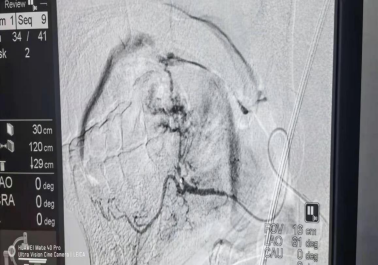

2021年4月5日下午,患者張大爺,舌根癌,之前已在山東省腫瘤醫(yī)院進(jìn)行了5周期化療,患者及家屬了解到我院擁有瓦里安調(diào)強(qiáng)放療設(shè)備及武霞主任豐富的放療經(jīng)驗,慕名而來。武主任通過查體及詢問病情,與患者溝通并強(qiáng)烈建議患者入院行放療,并告知及可能出現(xiàn)的風(fēng)險,患方表示了解并同意入院。

當(dāng)天晚上8:00,患者突然出現(xiàn)舌根部出血不止,入院血壓為70/50mmHg ,四肢濕冷。值班醫(yī)師在給予患者緊急查血、輸血、止血等糾正休克的同時,與我院介入醫(yī)學(xué)科金澤山主任溝通患者病情,金澤山主任認(rèn)為急需介入止血治療,金主任犧牲個人休息時間立即趕到醫(yī)院,組織訓(xùn)練有速的介入醫(yī)學(xué)科團(tuán)隊進(jìn)行介入止血搶救工作。經(jīng)過介入醫(yī)學(xué)科與腫瘤科的緊密合作,患者舌根部止血成功,生命體征恢復(fù)正常,于23時50分患者轉(zhuǎn)危為安,安返病房。這只是臨沂市第三人民醫(yī)院的一個縮影,體現(xiàn)了患者與醫(yī)生之間的相互信任、科室之間的團(tuán)結(jié)合作、勇于擔(dān)當(dāng)?shù)氖姑?zé)任,臨沂市第三人民醫(yī)院秉承“不忘初心、牢記使命、永不懈怠”的精神,永遠(yuǎn)為沂蒙百姓的健康保駕護(hù)航。